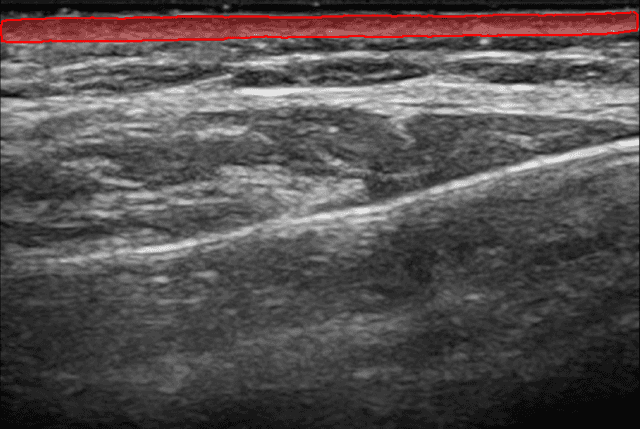

Escaneo de Precisión en 60 Segundos

Nuestra IA segmenta instantáneamente tu capa dérmica. Obtén mediciones precisas de el grosor y el área de la dermis.